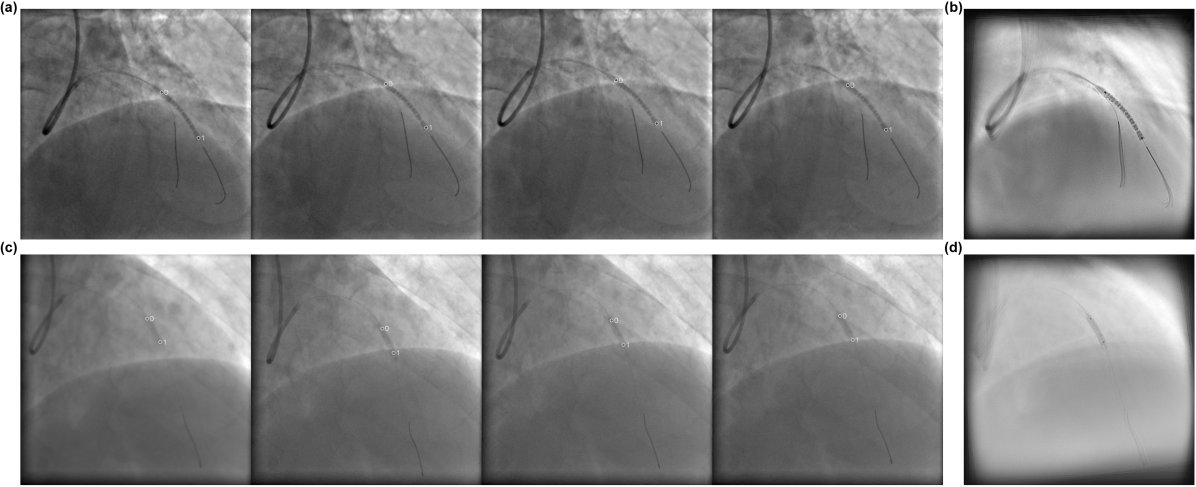

We used a fixed threshold cutoff (0.6) for identifying positive predictions (i.e. markers with probability greater than 0.6 were selected) to calculate the evaluation metrics shown in Table 1, 2, and 6. Here, we also demonstrate the performance of CenterTrack and our method (Table 5 and Table 5) when two markers with the highest probabilities in each frame were identified as markers detected, since it is the most straightforward way to identify a single stent based on the outputs of neural networks. Fig. 3 shows examples of tracking results from CenterTrack and the proposed method with this top-2 selection criterion, and the stent enhancement results based on the tracking results. It can observed that false positives dramatically affect enhancement results (Fig. 3b) and our method has a high precision score (Table 5 and Table 5), which demonstrates its robustness in clinical applications. Lower two rows of Fig. 3 show results of CenterTrack and the proposed method with representative MAEs (0.382 and 0.511) respectively. It can be observed that even though the MAE of our method is worse than that of CenterTrack, the enhancement results do not show much difference.

Refer to caption

Figure 3: Example tracking results (4 frames) from CenterTrack (a,e) and the proposed method (c,g), and the corresponding stent enhancement results (b,f) and (d,h). 7 frames were used for enhancement in all cases.